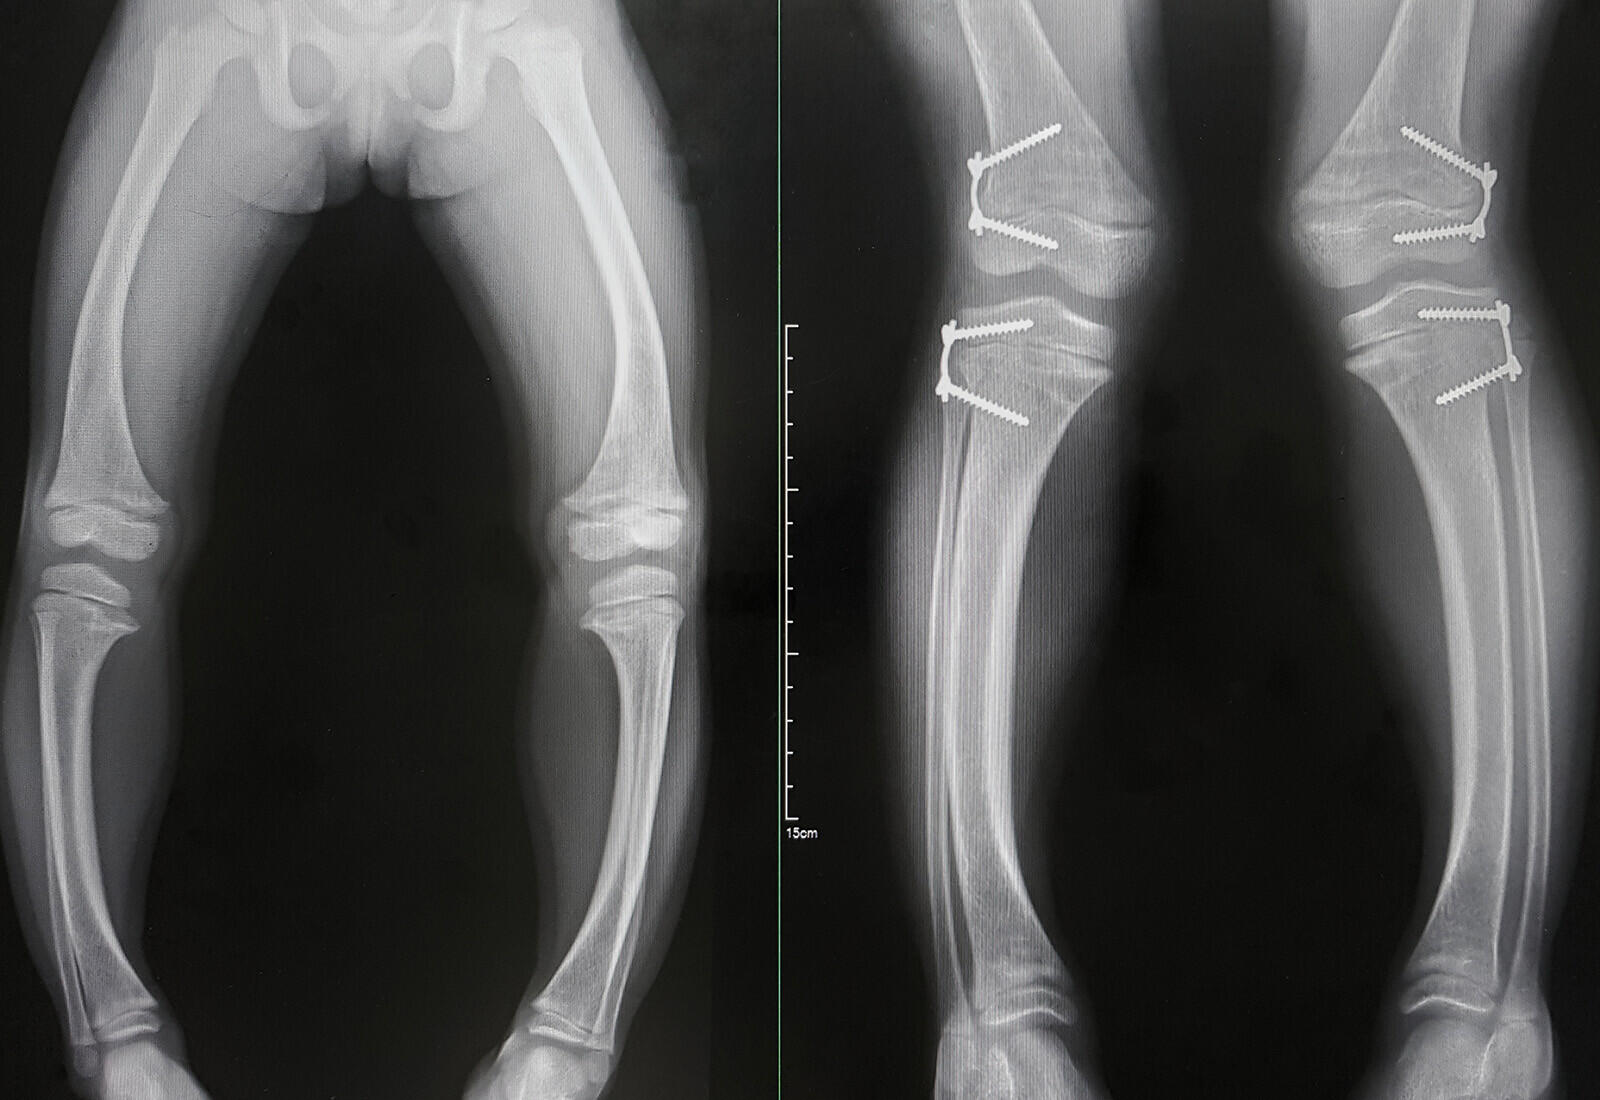

2. Rakitis & Vitamin D: Menemukan Cahaya dalam Kegelapan

Pada zaman ke-19, anak-anak seringkali terkena rakitis, penyakit yg menciptakan tulang mereka lemah & mudah patah. Masyarakat pada waktu itu tidak tahu apa penyebabnya, tetapi ada yg mencurigai kaitannya dengan kurangnya sinar matahari. Ternyata, vitamin Dyang kita dapat dari paparan sinar matahariadalah kunci untuk mencegah rakitis.

Pada 1920-an, ilmuwan seperti Elmer McCollum mulai menghubungkan paparan sinar mentari dengan kesehatan tulang. Vitamin D, yg kini diketahui sebagai “vitamin matahari”, menolong tubuh kita menyerap kalsium & fosfor, yg sangat penting untuk pembentukan tulang yg kuat. Jadi, kita dapat bilang vitamin D adalah teman baik kita ketika berjemur di bawah sinar matahari!